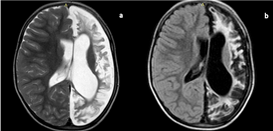

Figure 2 Sturge–Weber syndrome.

Axial FLAIR (a) shows thick sulcal hyperintensities in right fronto-parietal and temporo-occipital lobe showing significant post contrast leptomeningeal enhancement. (b) These areas show prominent ipsilateral sulci, sylvian fissure and subarachnoid space compared to the contralateral side. However, no ex vacuo dilatation of ipsilateral lateral ventricle is observed. FLAIR, fluid-attenuated inversion recovery.